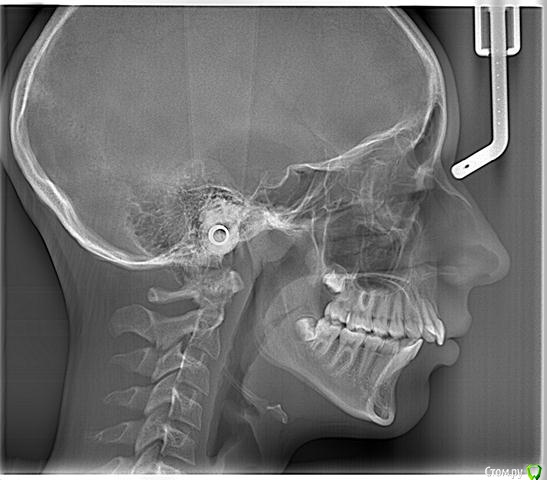

lulana Опубликовано 13 октября, 2015 Автор Поделиться Опубликовано 13 октября, 2015 (изменено) Only braces. Трг конечно увидеть надо ,но тут либо удаление 4 зубов вам светит либо ищите доктора владеющего meaw или tweed техникаСпасибо за ответ!С доктором владеющим meaw техникой, мы познакомились, но ещё не определилиь точно... Вопрос ещё такой возник: можно ли начинать лечение на брекет-системе незамедлительно, или стоит подождать до полных 12-ти лет, в связи с формированием (закрытием?) корней зубов? Вчера сделали ТРГ, прилагаю, может появятся ещё версии. Изменено 13 октября, 2015 пользователем lulana Ссылка на комментарий

Force Опубликовано 16 октября, 2015 Поделиться Опубликовано 16 октября, 2015 1. Трейнерами не избавляются от привычек и уж тем более не лечат такую скелетную деформацию. От привычек номер один - хороший психотерапевт. Плюс нормализация носового дыхания (КТ + грамотный лор-эндоскопист)2. Полная реконструкция прикуса после конусно лучевой томографии и полного анализа. с MEAW должен быть опытный пользователь. Не удалять четверки ни в коем случае. Добавлю конкретики в свои вопросы:1. Можно ли в нашем случае пробовать исправлять трейнерами (например Т4К или Т4А), био-блоками доктора Мью? Так как от вредных привычек мы ещё не избавились: привычка дышать ртом, грызть ногти, ручка, карандаши и пр., возможно вышеперечисленные приспособления нам помогут?2. Если вариант только с установкой брекет-системы, то можно ли устанавливать сейчас, или подождать как минимум до полных 12 лет? 1 Ссылка на комментарий